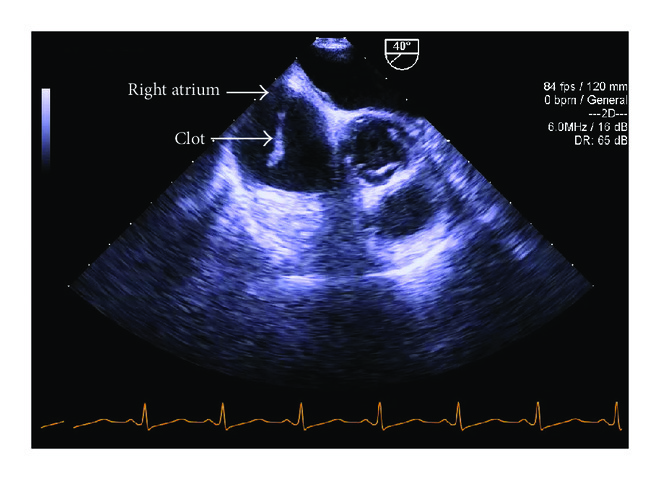

Six hours after induction, during dissection of the liver, the midesophageal bicaval TEE view demonstrated a mobile serpiginous fibrous clot, 2.5 cm × 1 cm, in the right atrium (Figure 2) which appeared to be attached to the 9 French catheter placed in the right internal jugular vein (Figure 3).

We confirmed the presence of the clot using different TEE views (Figure 4). A discussion ensued between the surgical and anesthesia teams as to how to best proceed with the case. Options included the use of rTPA, cardiopulmonary bypass, thrombectomy, and IV heparin administration. Until this point, the patient had been hemodynamically stable. Point of care blood gas analysis did not reveal any abnormalities. Repeat TEE evaluation revealed a slight increase in clot size but the patient’s hemodynamic status remained stable. Right and left ventricular function was not affected. The patient did not have any signs of increased pulmonary arterial pressure. Ultimately, it was decided to administer an initial bolus of 5000 units of IV heparin followed by a continuous infusion with a target aPTT of >60 seconds.